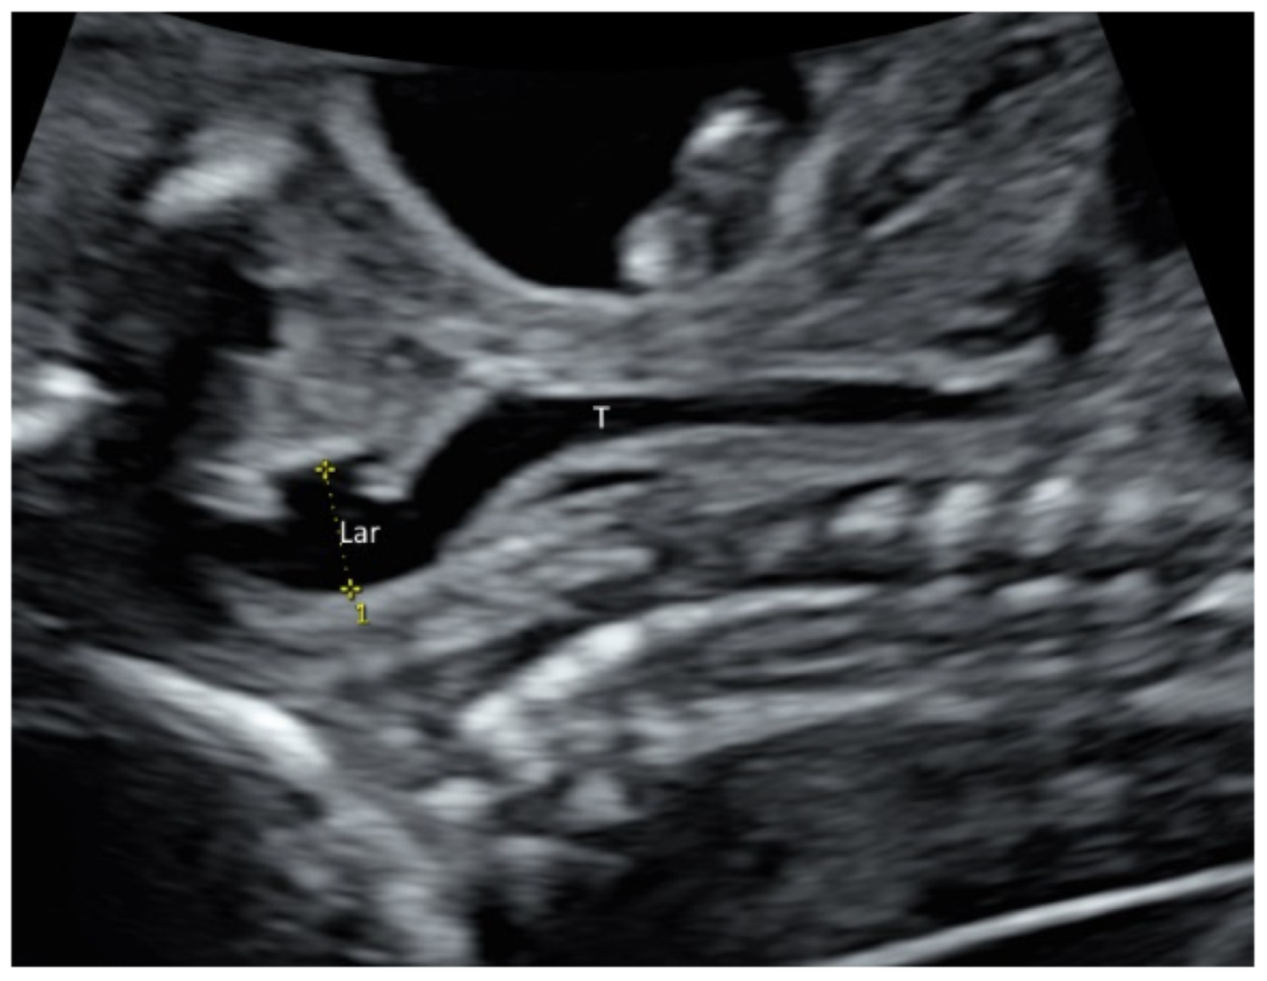

Larynx and its movement can be assessed by prenatal ultrasound (Figure 4 and Video S4). In at-risk fetuses such as those with laryngeal atresia [17] and congenital diaphragmatic hernia, prenatal ultrasound allows systematic examination of the larynx, including vocal cords to detect laryngeal anomalies [17,18].

Figure 4.

High-resolution ultrasonography of the fetal neck at 21 weeks’ gestation: sagittal view showing larynx (Lar) and trachea (T).